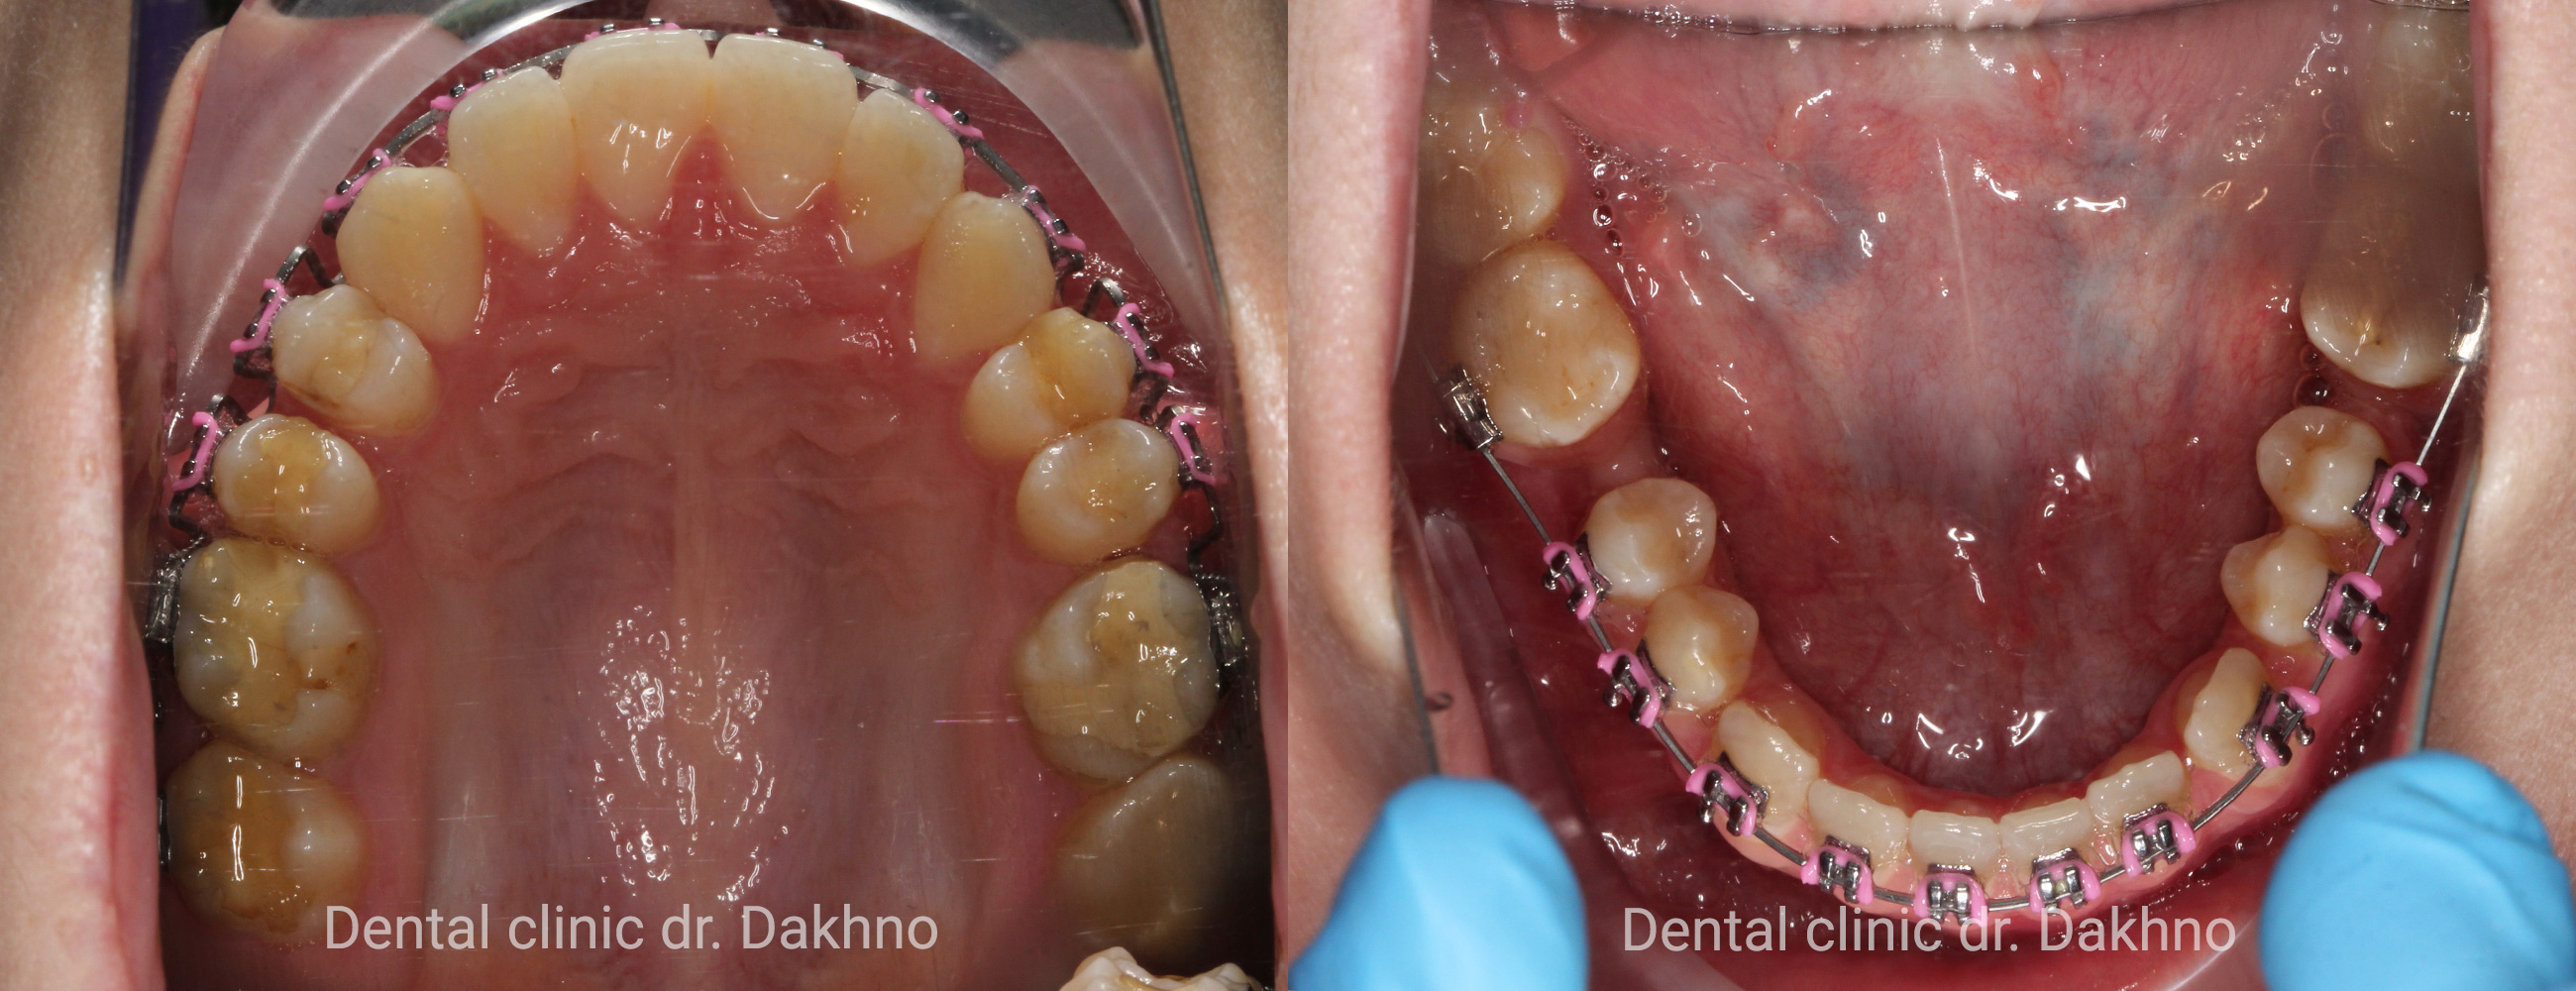

Вересень 2017. Перший етап ортодонтичного лікування спрямований на структурне розширення верхньої щелепи за рахунок фіксованого апарату HYREX на оклюзійних накладках, що дозволило відразу ж приступити до ортодонтичного лікування нижньої щелепи за допомогою фіксованої брекет-системи.

Жовтень 2017 Закінчено розширення та стабілізація потрібної ширини верхньої щелепи. Знятий апарат з верхньої щелепи. Потрібно відзначити, що Ксенія сумлінно ставилася до I етапу ортодонтичного лікування і ретельно доглядала за зубами і конструкціями, що дозволило зберегти здорову емаль зубів. Оскільки Ксенія відповідально відноситься до гігієни порожнини рота лікар-ортодонт Мітюріна Тетяна Володимирівна прийняла рішення про впровадження двох мікроімплантів в область премолярів на нижній щелепі для мезіалізації других молярів.

Лютий 2018 Продовження ортодонтичного лікування. Фіксована брекет-система на зуби верхньої щелепи.

Березень 2018 Продовження ортодонтичного лікування. Фіксація дуг з петлями. Ксенія навчена фіксувати еластики по III класу.